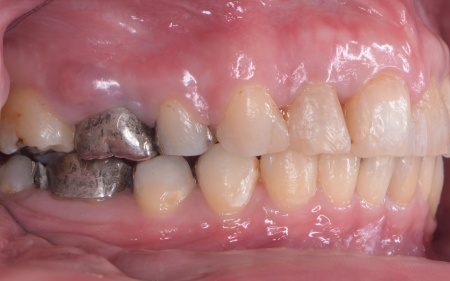

30代女性 出っ歯と開咬に対しアンカースクリューを用いたワイヤー矯正で治療した症例

拝見したところ、上前歯が大きく前に出ている上顎前突であり、上下の前歯が噛み合わずに口を閉じても前歯同士が接触しない「開咬(かいこう)」の状態でした。

上顎の奥歯(第1小臼歯)を左右1本ずつ抜き、奥歯にアンカースクリューを埋め込みます。上奥歯をしっかりと固定することで、抜歯で確保したスペースを最大限に活用しながら、前歯を効率よく後方へ牽引することが可能です。

治療の結果、前歯が正しく噛み合うようになり、横顔のバランスも整いました。